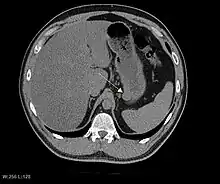

CT scanning is often undertaken (see the radiology section).

The purpose of radiologic imaging is to locate the lesion, evaluate for signs of invasion and detect metastasis. Features of GIST vary depending on tumor size and organ of origin. The diameter can range from a few millimeters to more than 30 cm. Larger tumors usually cause symptoms in contrast to those found incidentally which tend to be smaller and have better prognosis.[4][20] Large tumors tend to exhibit malignant behavior but small GISTs may also demonstrate clinically aggressive behavior.[21]

Barium fluoroscopic examinations and CT are commonly used to evaluate the patient with abdominal complaints. Barium swallow images show abnormalities in 80% of GIST cases.[21] However, some GISTs may be located entirely outside the lumen of the bowel and will not be appreciated with a barium swallow. Even in cases when the barium swallow is abnormal, an MRI or CT scan must follow since it is impossible to evaluate abdominal cavities and other abdominal organs with a barium swallow alone. In a CT scan, abnormalities may be seen in 87% of patients and it should be made with both oral and intravenous contrast.[21] Among imaging studies, MRI has the best tissue contrast, which aids in the identification of masses within the GI tract (intramural masses). Intravenous contrast material is needed to evaluate lesion vascularity.

Preferred imaging modalities in the evaluation of GISTs are CT and MRI,[23]: 20–21 and, in selected situations, endoscopic ultrasound. CT advantages include its ability to demonstrate evidence of nearby organ invasion, ascites, and metastases. The ability of an MRI to produce images in multiple planes is helpful in determining the bowel as the organ of origin (which is difficult when the tumor is very large), facilitating diagnosis.

As the tumor grows it may project outside the bowel (exophytic growth) and/or inside the bowel (intraluminal growth), but they most commonly grow exophytically such that the bulk of the tumor projects into the abdominal cavity. If the tumor outstrips its blood supply, it can necrose internally, creating a central fluid-filled cavity with bleeding and cavitations that can eventually ulcerate and communicate into the lumen of the bowel. In that case, barium swallow may show an air, air-fluid levels or oral contrast media accumulation within these areas.[21][25] Mucosal ulcerations may also be present. In contrast-enhanced CT images, large GISTs appear as heterogeneous masses due to areas of living tumor cells surrounding bleeding, necrosis or cysts, which is radiographically seen as a peripheral enhancement pattern with a low attenuation center.[20] In MRI studies, the degree of necrosis and bleeding affects the signal intensity pattern. Areas of bleeding within the tumor will vary its signal intensity depending on how long ago the bleeding occurred. The solid portions of the tumor are typically low signal intensity on T1-weighted images, are high signal intensity on T2-weighted images and enhanced after administration of gadolinium. Signal-intensity voids are present if there is gas within areas of necrotic tumor.[22][26][27]